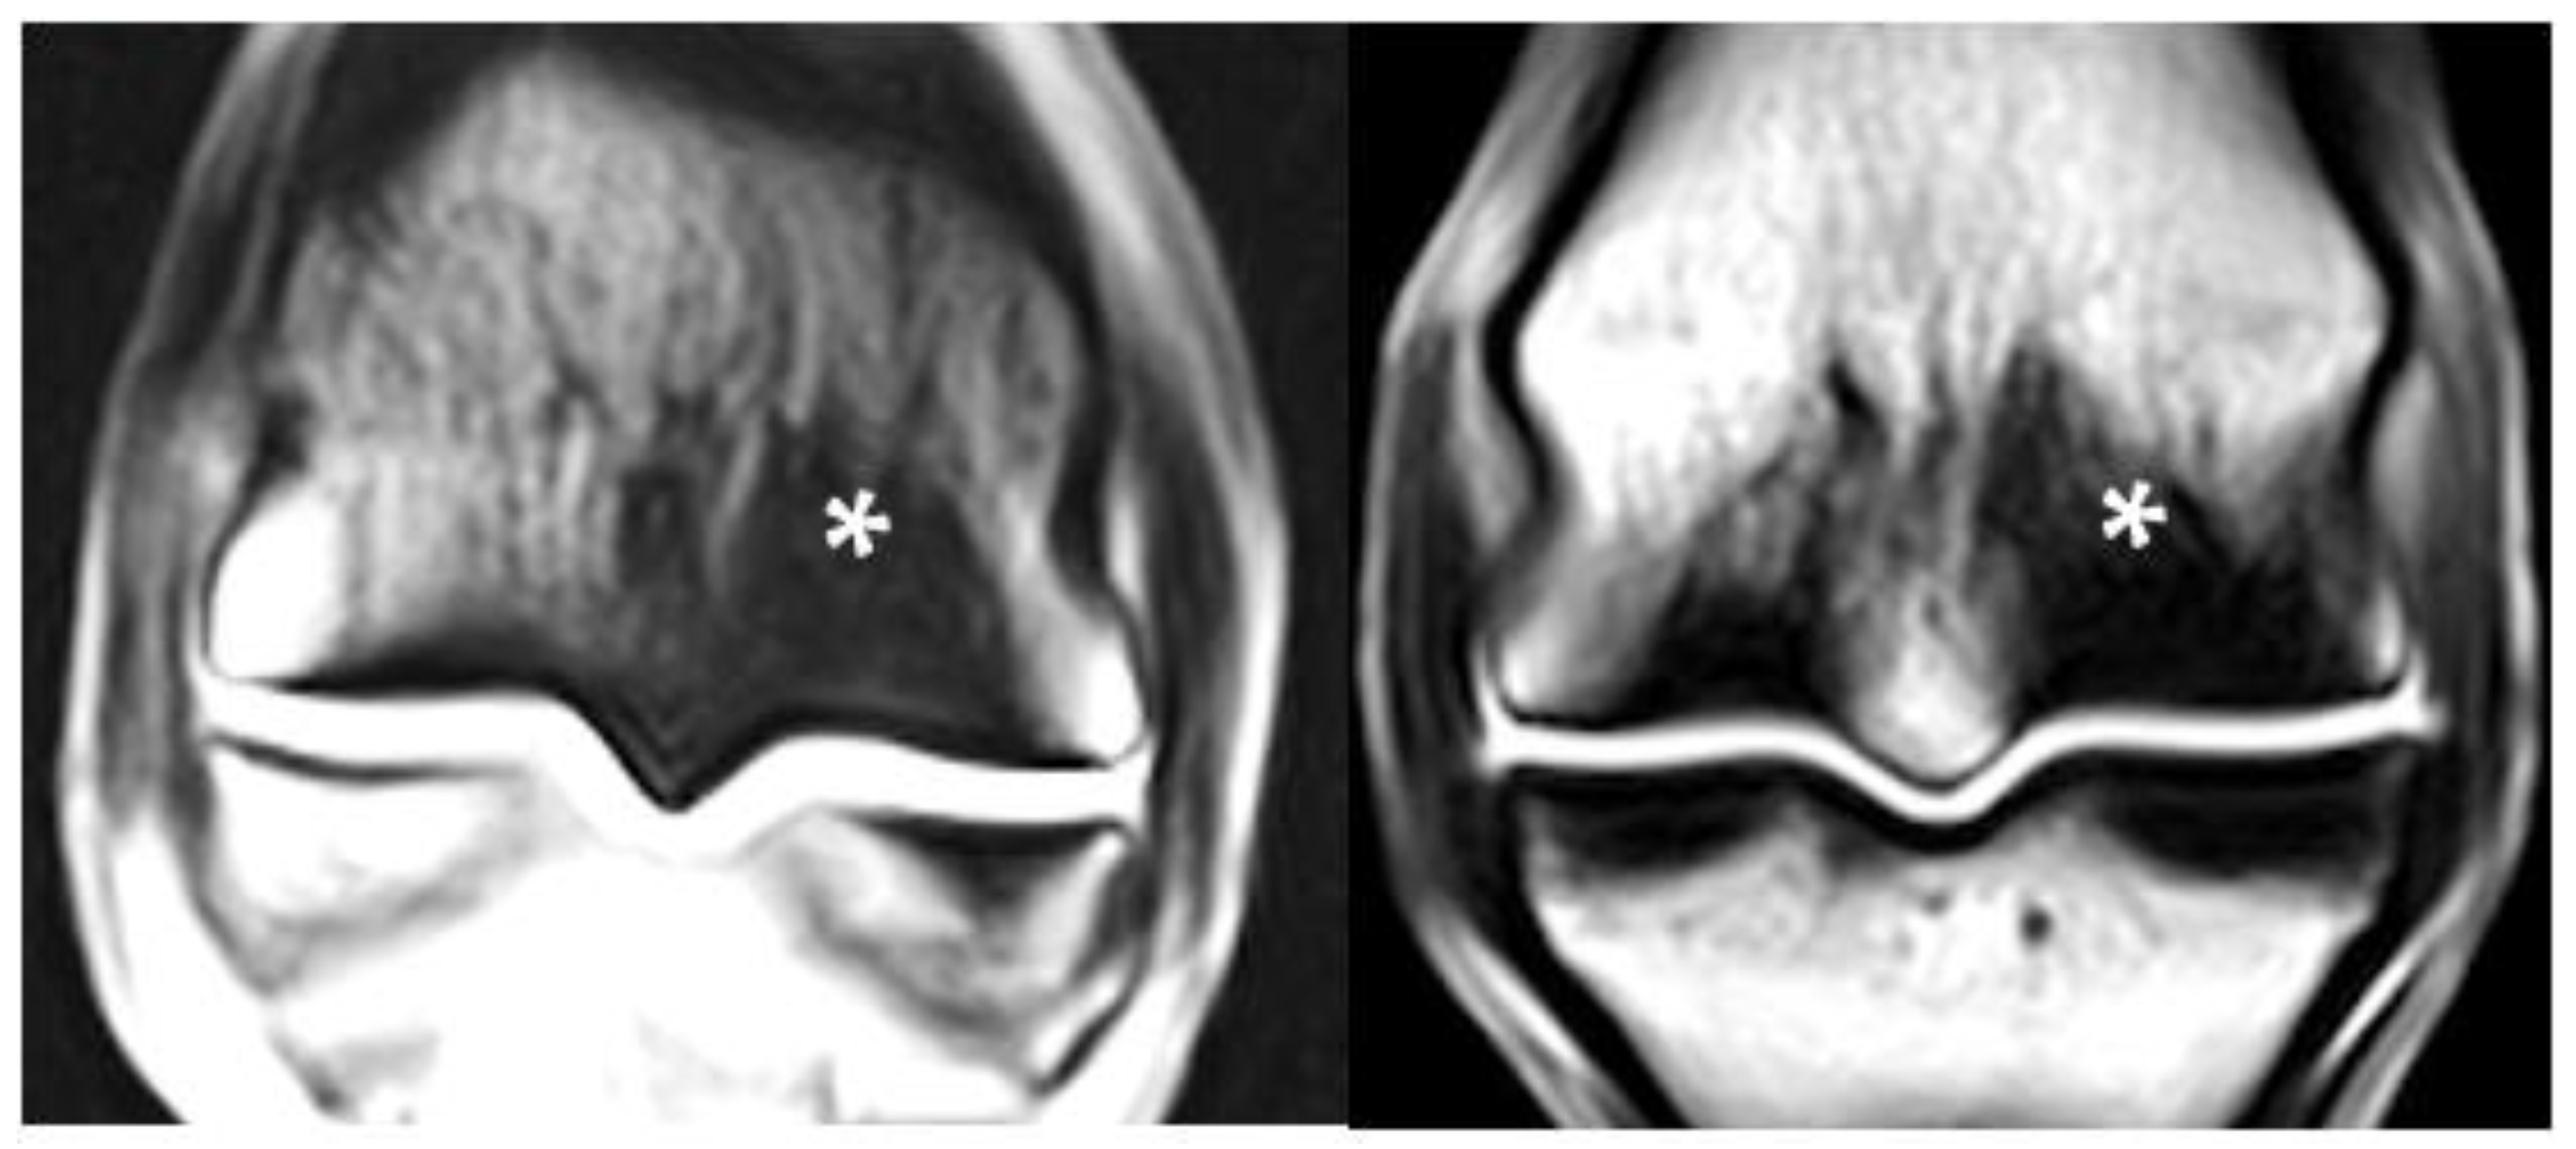

3.5. PSG Cartilage Defects

3.6. PSG STIR Hyperintensity